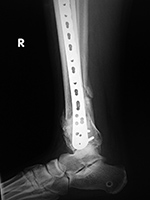

43 year-old man with comminuted right tibia and fibula fractures as well as extensive bone loss and soft tissue injury. A tibial intramedullary nail with proximal and distal locking screws is present as well as multiple rounded bony allografts. There are also large skin staples.

Right tibia bone graft